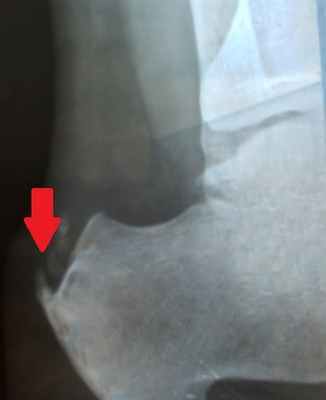

Уточнить диагноз позволяет рентгенография стопы. При этом на рентгенограмме виден костный нарост.

После консультации диагноз «пяточная шпора» подтвердился – на рентгеновском снимке костный нарост был четко виден. На приеме специалисты клиники объяснили женщине: методы, на которые она возлагала надежды, эффективны только в самом начале заболевания. А так как Наталье Борисовне пяточная шпора не один год мешает нормально жить, операция была единственным верным решением. Более того, медлить с вмешательством было ни в коем случае нельзя.

Ренген-снимок до операции Рентген стопы после операции

Диагностикой и лечением пяточной шпоры занимается врач ортопед. Основным способом выявить патологию и оценить степень ее развития является рентгенография. На снимке хорошо виден костный нарост, его форма, расположение и величина.

После изучения истории болезни, жалоб пациента, врач проводит осмотр ноги: наличие высокого свода, площадь болезненности в области пятки, наличие ограничений подвижности в стопе. Для верификации диагноза могут потребоваться инструментальные методы исследования. Рентгенография позволяет получить четкое изображение костных тканей. Это метод исследования дает возможность исключить другие причины болей в пятке,такие как перелом или артроз. Пяточная шпора хорошо визуализируется при рентгенографии.